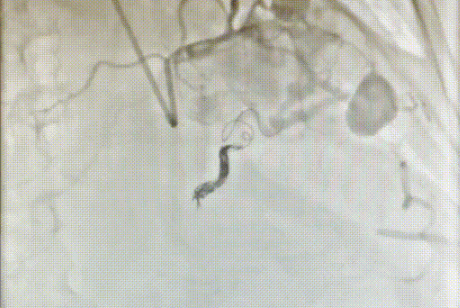

完善治疗前准备后,徐先增团队于28日为赵奶奶实施了介入治疗。治疗中,徐先增细致操作,将出血的4个动脉瘘一一定位,用8个弹簧圈将它们补上,顺利完成止血,过程中未对血管造成任何伤害。经查,赵奶奶的动脉已不再出血。